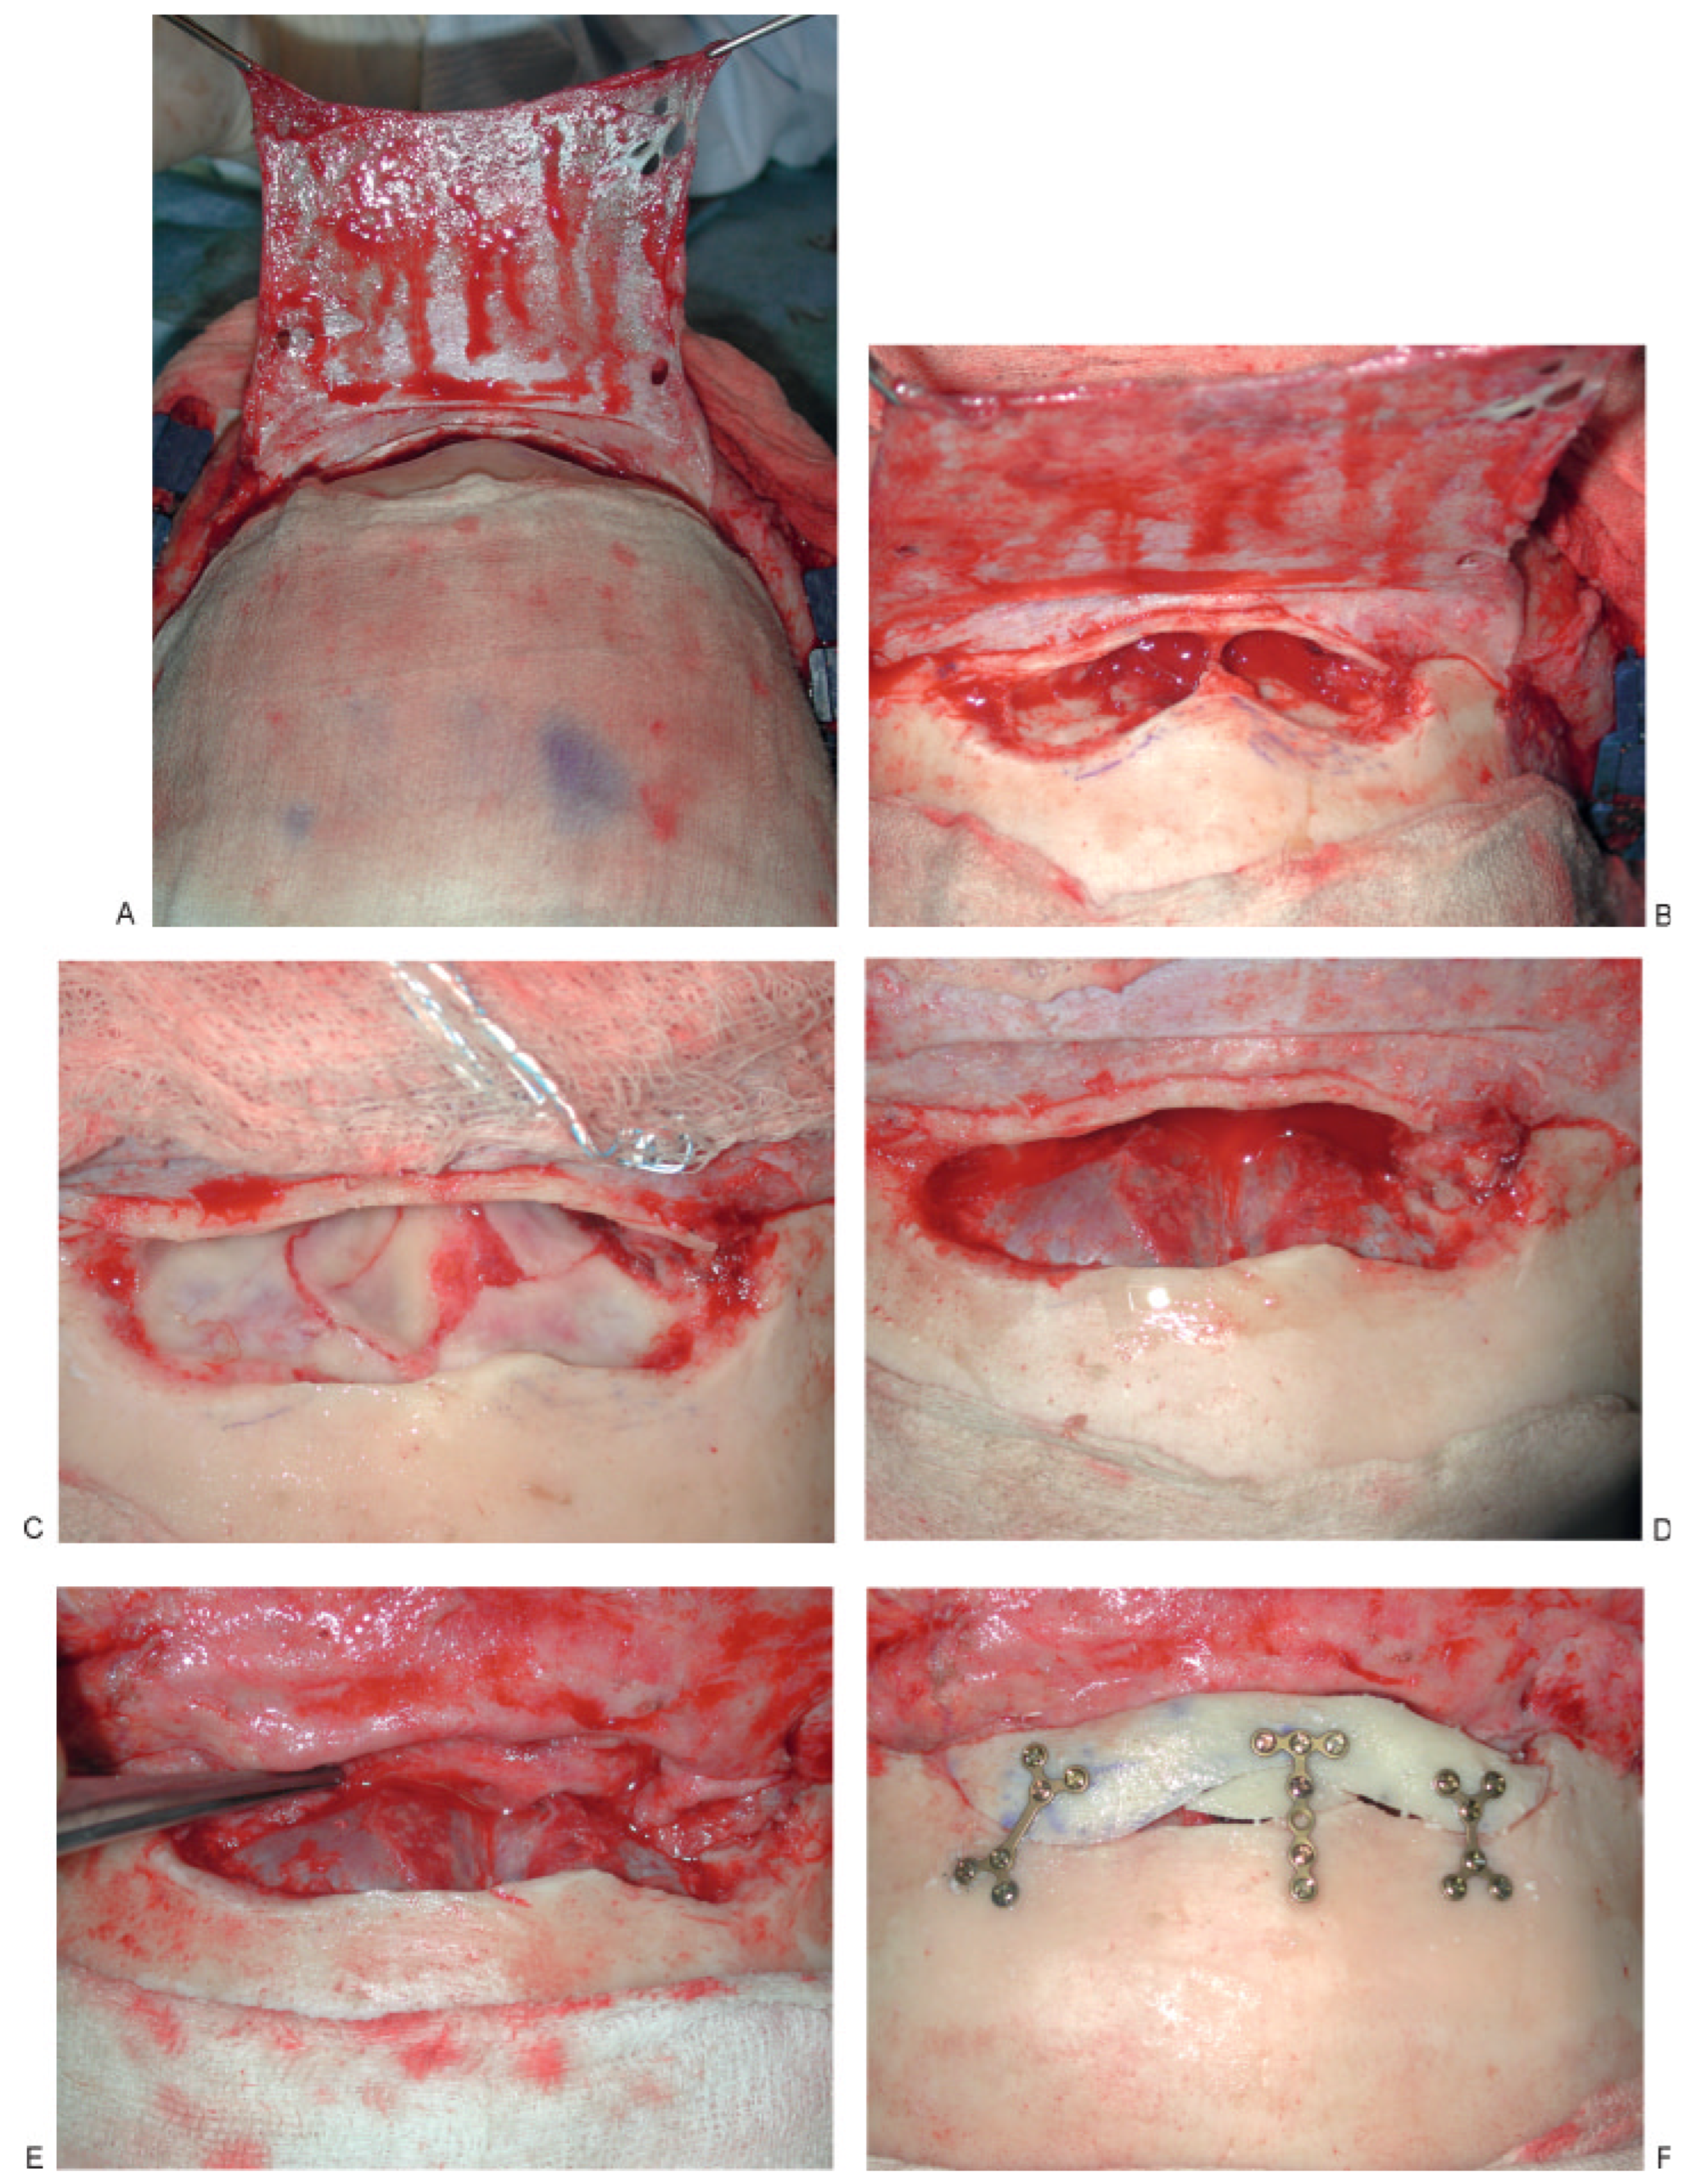

Prevention is the best treatment, and fastidious removal of mucosa and/or a patent drainage system is necessary to create a safe sinus. The most serious skullbase complication is cerebral spinal fluid (CSF) leak [20]. Most of the time this is transient, but it may be persistent and require cranialization and dural repair (Figure 6) [21,22]. The two areas most commonly affected are the cribriform plate where the dura is densely adherent and the foveae ethmoidalis where the bone is thinnest and sometimes dehiscent [23]. Devastating consequences of unrecognized or untreated CSF leak include meningitis, encephalitis, and epidural and/or subdural abscess. Proper imaging with high-resolution CT scanning, cisternography, fluorescein endoscopy, and a high index of suspicion is often necessary to make this diagnosis. Subtle CSF rhinorrhea may be the only presenting symptom. Image-guided endoscopy may be helpful as well as fluid collection testing for β-2-transferrin [24].

Figure 6.

Anterior and posterior table fracture with comminution and displacement of posterior table with CSF leak. (A) Elevation of pericranial flap, (B) comminution of posterior table with CSF leak, (C) posterior table fracture with dural tear, (D) cranialization with repair of dura, (E) placement of pericranial flap to separate anterior skull base from nasal cavity, (F) reconstruction of anterior table.